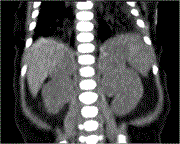

Bilateral adrenal hemorrhage after pancreaticoduodenectomy

Sarah Andres and others

Journal of Surgical Case Reports, Volume 2023, Issue 7, July 2023, rjad411, https://doi.org/10.1093/jscr/rjad411